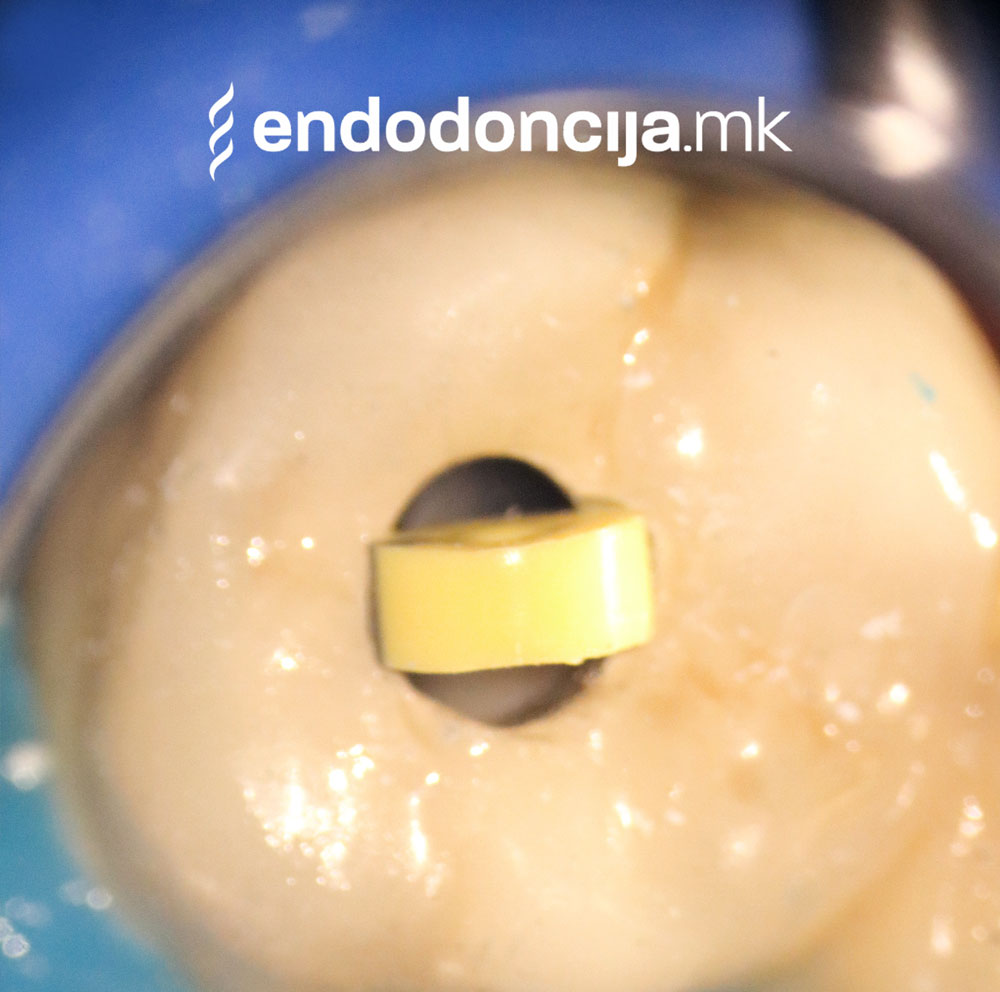

За време на претходните третмани, забот не само што бил ослабен со механички третман на коренскиот канал, туку и со поставување и закотвување на забното колче. Кога се ревидира третманот со коренскиот канал, овие колчиња треба да се отстранат колку што е можно повнимателно за да се задржи важната забна супстанција.

Она што е импресивно е прецизноста на микроскопските третмани. Дури и кога каналите се потешко достапни, може да се лоцираат и исчистат така што релапсите се со помала веројатност. Спротивно на тоа, скриените канали често остануваат неоткриени во конвенционалниот третман на коренскиот канал и затоа не можат да се чистат. Бактериите можат да се размножуваат таму без пречки и да предизвикаат воспаленија. Ова често останува незабележано со години додека не се појави забоболка, а со тоа и компликации.

Употребата на микроскоп исто така овозможува детектирање пукнатини или фрактури што може да предизвикаат болка или воспаление.